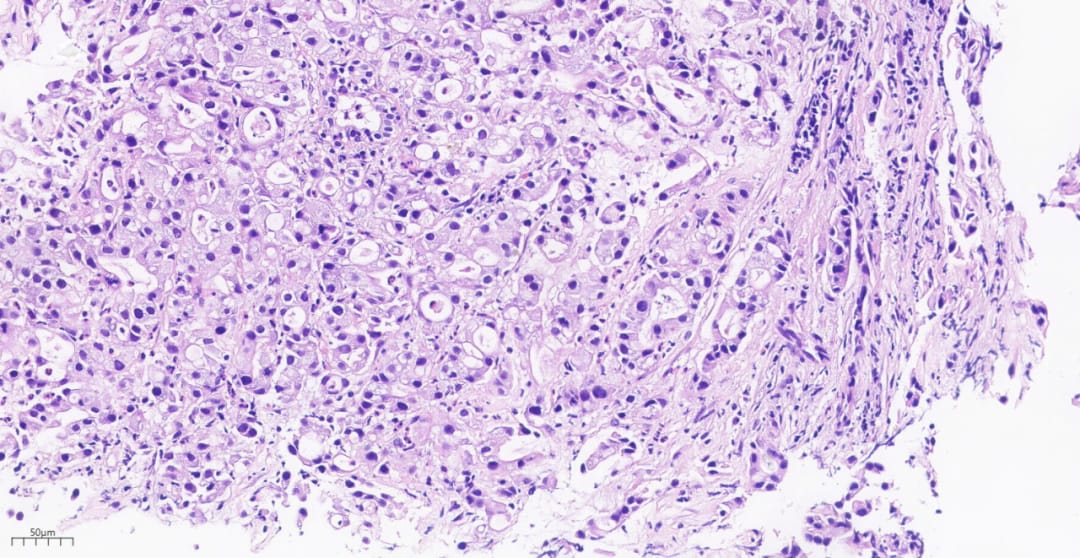

为了明确病变的性质,医生对患者进行了组织病理活检。在显微镜下,病理医生观察到肿瘤细胞形态异常,排列混乱,呈现出低分化腺癌的特征。这些细胞体积较大,细胞核异型明显,显示出高度的恶性潜能。

图2 显微镜下的肿瘤组织呈弥漫片状分布

图3 肿瘤细胞排列紧密

图4 肿瘤细胞排列成复杂的腺体形态

图5 部分肿瘤细胞排列成腺样结构

图6 高倍镜下可见明显的细胞异型性

- 病理形态: 在显微镜下,肿瘤细胞黏附性差,常呈片状或岛状分布,显示出高度的异型性。